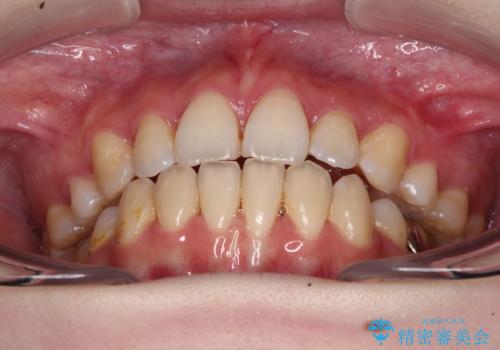

目立たない裏側矯正で突出感を改善 ハーフリンガル矯正

- ハーフリンガル

- 口元の突出感を気にして来院された患者様です。

上下左右の第一小臼歯4本を抜歯して口元を下げる治療計画としました。

裏側矯正特有の抜歯スペースに前後の歯が倒れ込む状態が長く続き、改善に長期間を要しました。